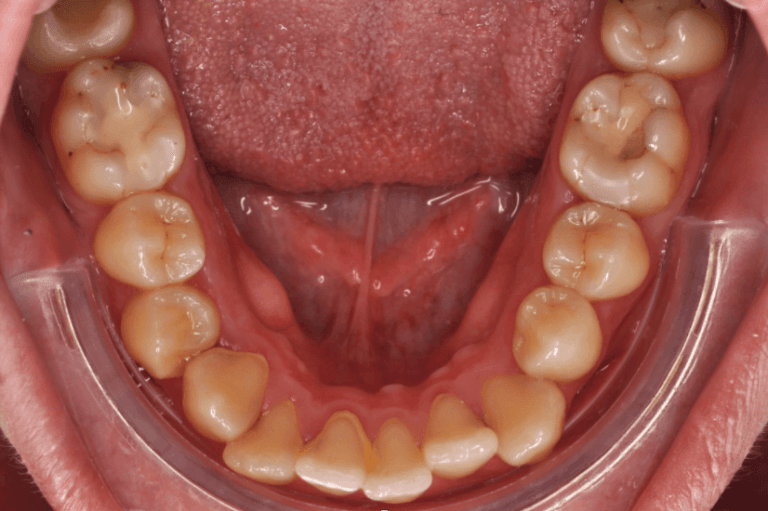

Kako slike obično govore više od reči, na sledećim slikama možete pogledati sjajne rezultate postignute nošenjem fiksnih proteza kod jednog našeg pacijenta: